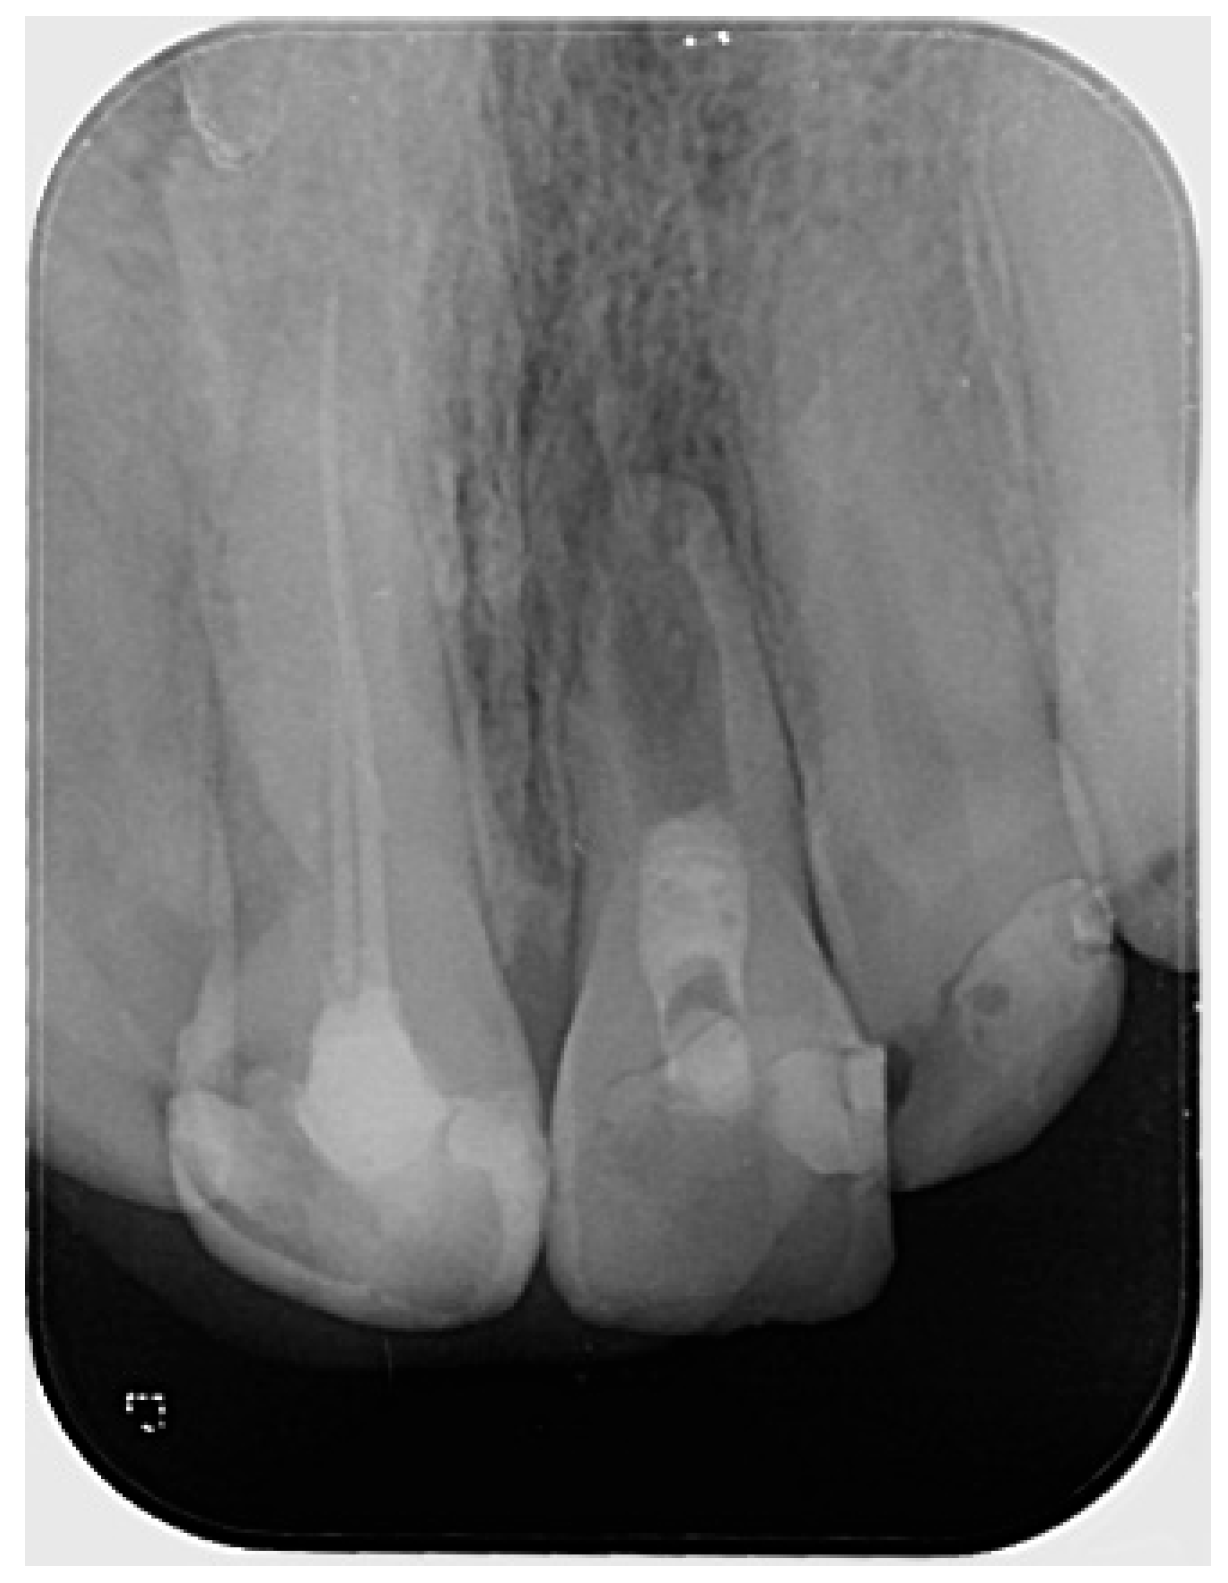

The periapical radiograph showed that tooth #21 had undergone previous endodontic treatment. A diffuse periapical radiolucency was observed surrounding the open apex. Additionally, the root appeared relatively short and exhibited thinner dentinal walls compared to the adjacent tooth #11 (Figure 1).

Figure 1. Preoperative radiograph of tooth #21. The radiograph shows previous endodontic treatment, with the root canal filling material not extending to the full length of the canal. A diffuse radiolucency is visible around the open apex. (The mark in the lower left corner indicates the left side).